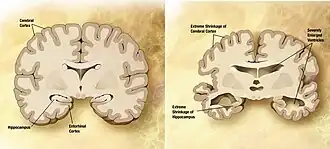

| Comparação entre um cérebro idoso normal (esquerda) e o cérebro de uma pessoa com Alzheimer (direita), estando assinaladas as características diferenciadoras | |

A doença de Alzheimer é caracterizada pela perda de neurónios e sinapses no córtex cerebral e em determinadas áreas subcorticais. Esta perda provoca a atrofia das áreas afetadas, incluindo degeneração no lobo temporal, no lobo parietal e em partes do lobo frontal e do giro do cíngulo.[54] A degeneração ocorre também nos núcleos do tronco cerebral, como o cerúleo.[90] Os estudos com IRM e TEP documentam diminuições no tamanho de determinadas áreas do cérebro à medida que a doença evolui de défice cognitivo ligeiro para Alzheimer, em comparação com imagens semelhantes de idosos saudáveis.[91][92]

Tanto as placas amiloides como os novelos neurofibrilares são claramente observáveis ao microscópio no cérebro de pessoas com Alzheimer.[93] As placas são depósitos densos e praticamente insolúveis de peptídeos beta amiloides e material celular no exterior e em redor dos neurónios. Os novelos são agregados de proteína tau associada aos microtúbulos que se tornou hiperfosforilada e se acumulou no próprio interior das células. Embora alguns idosos possam desenvolver placas e novelos devido ao processo de envelhecimento, o cérebro de pessoas com Alzheimer apresenta um número muito superior em áreas específicas, como no lobo temporal.[94] Os corpos de Lewy não são incomuns em pessoas com Alzheimer.[95]